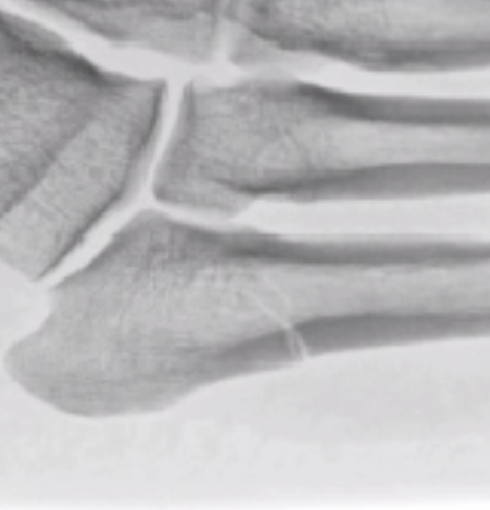

This case demonstrates that isolated fifth metatarsal shaft fractures in healthy, active adults can potentially be managed conservatively with excellent outcomes.